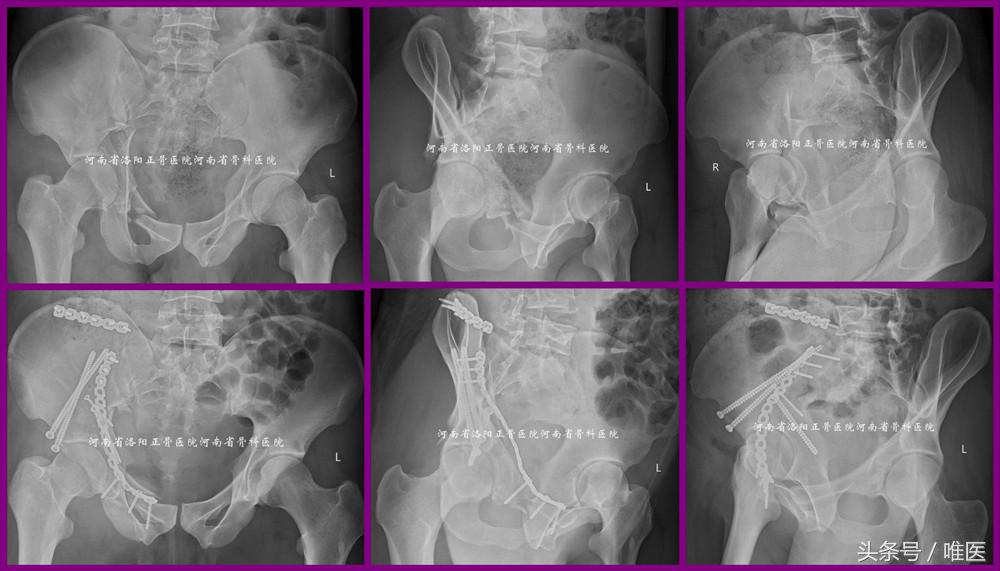

一例88岁女性病人因摔伤导致右半骨盆疼痛、右髋活动受限五天入院。其合并高血压病及心律失常。化验显示轻度贫血及低白蛋白,肝肾功能正常。彩超显示心脏功能正常,双下肢无静脉血栓形成。影像检查见图1。入院诊断:骨盆骨折(OTA-61B2.3):1.右侧髂骨新月形骨折;2.右侧耻骨上下支骨折。问:如何治疗?保守or手术?如手术,切开or闭合?每人都有自己的答案。但通过本期的讲解,相信大家会得出一个优选答案。

图1. 一例88岁女性骨盆骨折的影像资料。

病例1:即本文第一部分所述病例。术前影像资料见图1。术后影像资料见图11。病人术后第一天即坐起活动而有效地降低了卧床并发症。此处给出开篇问题的答案。

图11. LC-II螺钉的经皮置入技术用于治疗LC-II(即OTA-61B2.3)型骨盆骨折。